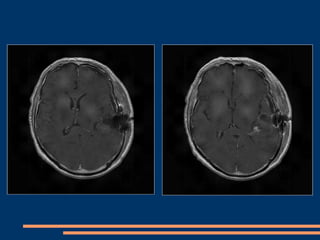

IRM post-opératoire à J 15